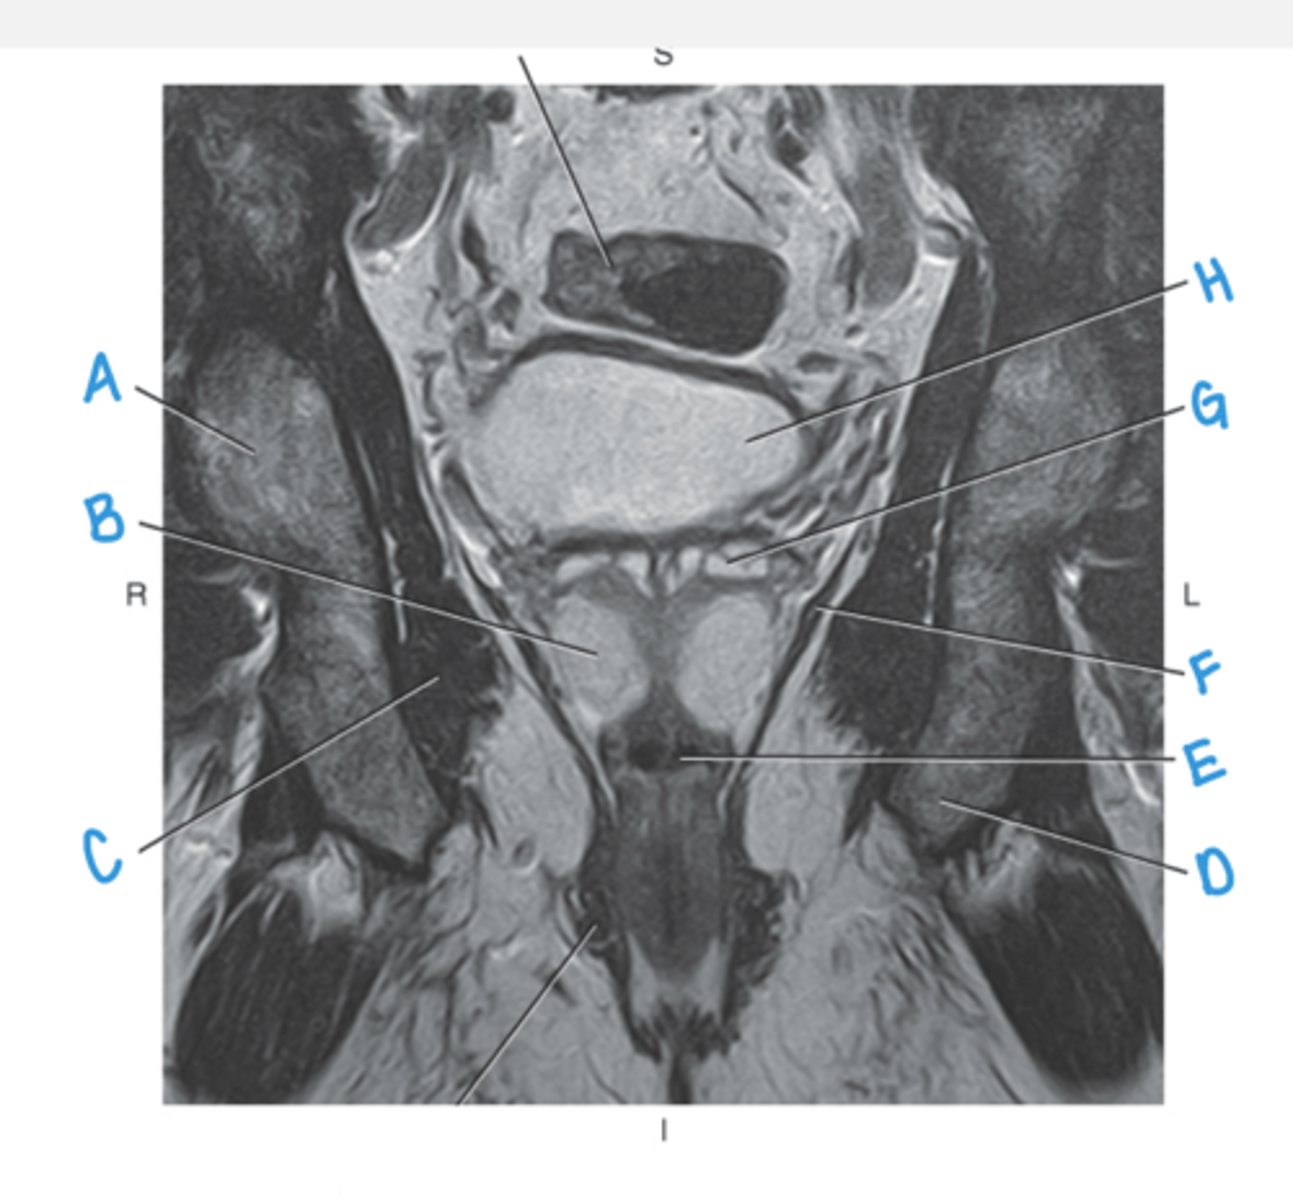

obturator externus muscle

A

obturator internus muscle

B

levator ani muscle (pubic diaphragm)

C

gluteus maximus muscle

D

pubic symphysis

E

rectus abdominus muscle

bladder

prostate

F